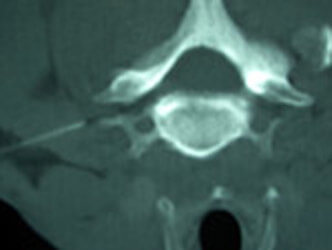

Bilder zu Injektionstherapie und CT-Injektionen

Bildwandlergesteuerte mikrotechnische Injektionstherapie und CT-Injektionen.

Je nachdem, ob Arthrose die Ursache für die Rückenbeschwerden ist oder ein Bandscheibenvorfall vorliegt, kann man mit einem Kontrastmittel zielgerichtet entsprechende Medikamente an den Ort der Ursache spritzen. Hierbei verwenden wir Mikro-Kanülen. Dieser Injektionsvorgang ist deutlich weniger schmerzhaft als eine vergleichbare Spritze in den Muskel.

Hier besteht ebenfalls wie bei dem uns zur Verfügung stehenden Computertomographen die Möglichkeit, z. B. auch entsprechende Knorpelsubstanzmittel direkt an den Ort des Verschleißes zu injizieren (CT-Injektionen). Darüber hinaus können abschwellende Medikamente oder gentechnologische Produkte an den Ort von Bandscheibenvorfällen appliziert werden, um so das bestehende ödem und daraus folgend den Nerv zu entlasten. Damit können Operationen häufig unnötig werden.